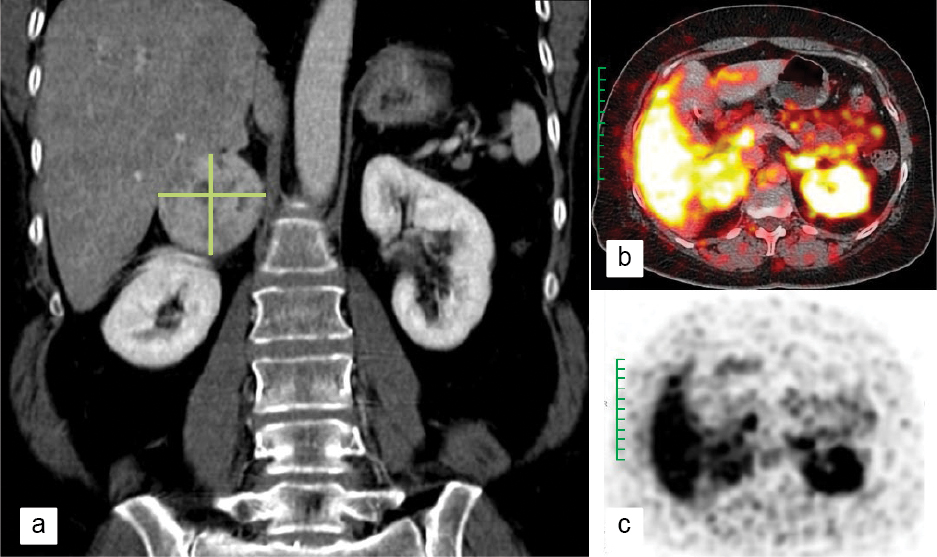

A 24-hour urinary fractionated metanephrines and normetanephrines of 966 µg and 4371 µg, respectively, clinched the diagnosis. 68-Gallium (68Ga)-DOTATOC-PET (position emission tomography) scan detected a mass lesion of about 5 × 6 cm (Fig. 1), with internal necrosis abutting the right adrenal gland, with no local or distant metastasis. Diagnosis of right adrenal pheochromocytoma was made. She was started on low-dose α-blocker. A β-blocker was later added before surgery. The mass was surgically removed 1 week later.

Figure 1. Right adrenal pheochromocytoma (marked in green) as seen in a) CT image, b) PET image and c) PET DOTATOC image.